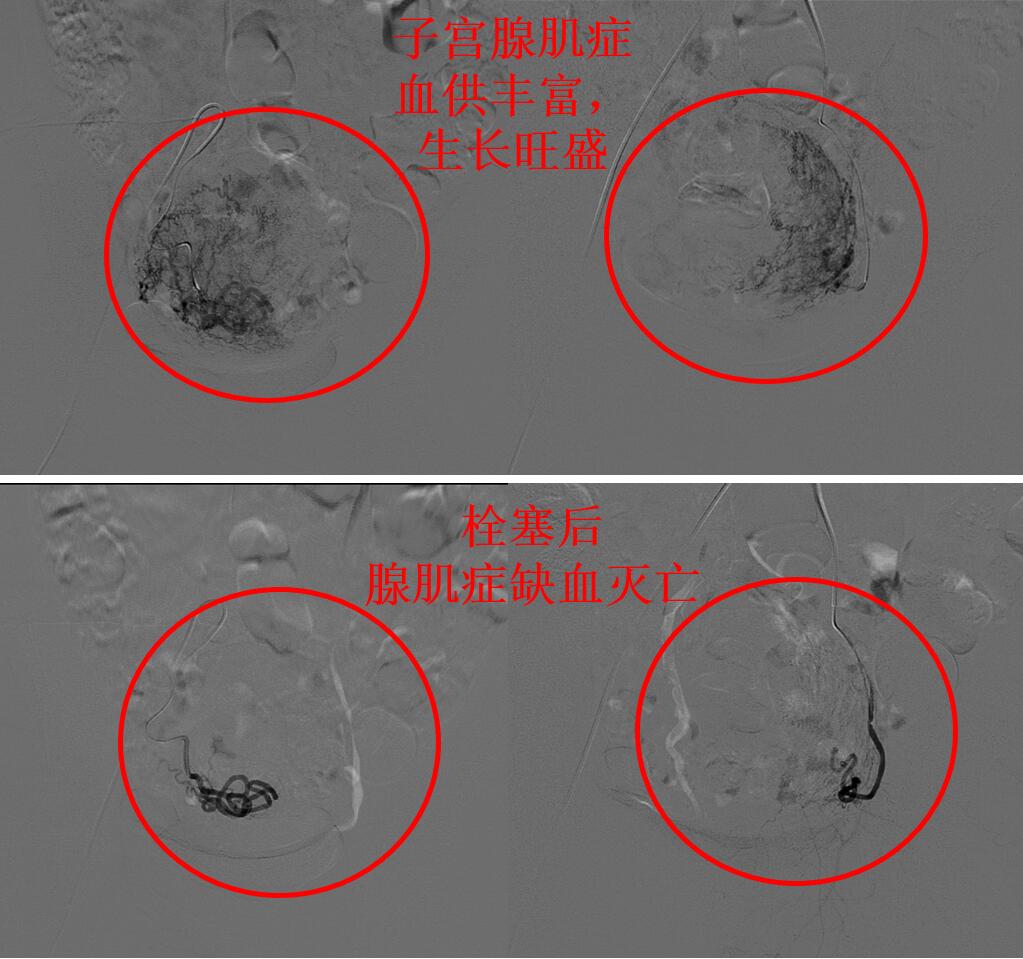

通过磁共振评估显示蓝护士的子宫腺肌症血供丰富,经大腿打针超选择栓塞子宫腺肌症的供血血管杀死腺肌症病灶会取得良好的疗效,则行子宫腺肌病介入超选择栓塞治疗(如下图)。